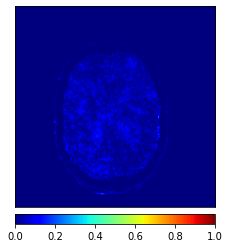

In this paper, we propose a bidirectional learning model, known as dual contrast cycleGAN (DC-cycleGAN), for medical image synthesis from unpaired data. Specifically, a dual contrast (DC) loss is formulated that leverages the advantage of samples from the source domain as negative samples to indirectly build constraints between real source and synthetic images via discriminators, and synthesize images more related to the target domain by enforcing the synthetic images to fall far away from the source domain. In addition, structural similarity index (SSIM) [35] and cross-entropy (CE) [48] are integrated into the DC-cycleGAN structure to avoid disappearing gradient information that is caused by a mean absolute error (MAE) and synthesizing irrelevant images. SSIM considers luminance [35] and CE converges fast as its back-propagation error is less than MSE [28]. As can be seen in Figs. 1 and 2, using SSIM and CE with dual contrast can generate more clear and accurate MR images as compared with that of MAE and MSE, and SSIM and CE without dual contrast loss. Although both SSIM and CE with dual contrast and without dual contrast generate similar CT images, SSIM and CE with dual contrast quantitatively generate better images as shown in Table 4. The experimental results indicate that DC-cycleGAN is able to consider more complex features such as structure in synthesizing images and produce remarkable results as compared with other state-of-the-art methods reported in the literature.

Tables 3 and 4 show the results of MR and CT synthesis, respectively. As can be seen, all components play vital role in both tables. SSIM & CE (w) performs significantly better than other losses in synthesizing MR images. This also can be seen visually in Fig. 1. In contrast, SSIM&CE (w) performs slightly better than SSIM&CE (wo) in synthesizing CT images, both generate more or less similar CT images (see Table 4).